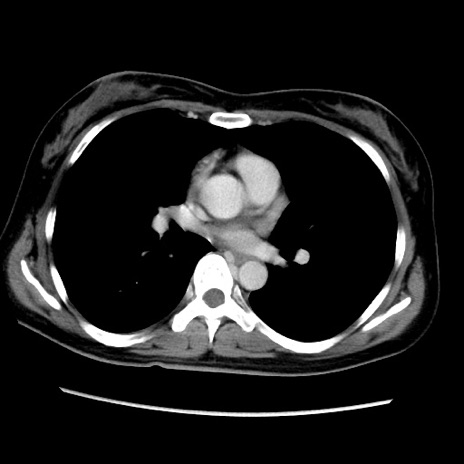

MRI(4日後)

【症例】40歳代女性

【主訴】上下腹部痛

【現病歴】2日目から下腹部痛あり。夜間は痛みで眠れなかった。昨日より上腹部痛と下痢が出現。臥位で痛みは軽快したため、休んでいた。本日になって臥位でも立位でも痛みが強くなってきたため救急要請。

【既往歴】子宮内膜症

【身体所見】部:平坦・軟、左上下腹部に圧痛あり、反跳痛あり。

【データ】WBC 21800、CRP 26.78